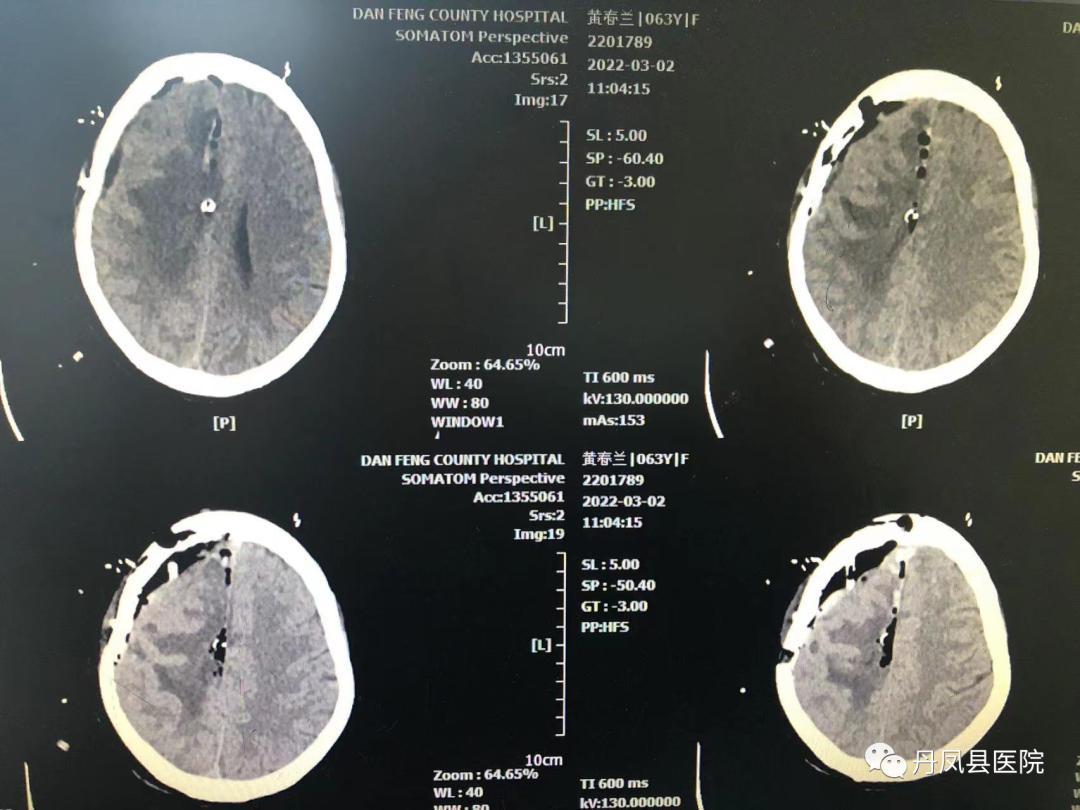

图为术中切除组织病检报告术后第二天,患者神志清楚,可以配合完成指令动作,复查CT显示:“颅内肿瘤全切”。目前,患者病情稳定,在肢体功能康复中。

![]()

术后复查CT显示:颅内肿瘤全切